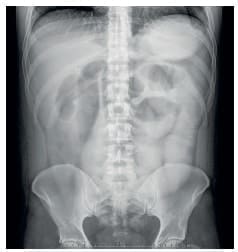

En el posoperatorio, el paciente se mantuvo con débitos altos por la sonda nasogástrica, por lo que al quinto día se solicitó un tránsito intestinal con gastrografina, sin existir progresión del contraste en el intestino delgado, con falta de vaciamiento gástrico (Figura 2).

Figura 2. Imagen radiológica que muestra la falta

de progresión del medio de contraste.